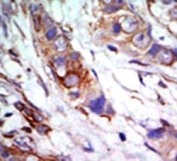

IHC analysis of FFPE human breast carcinoma tissue stained with the ERK5 antibody